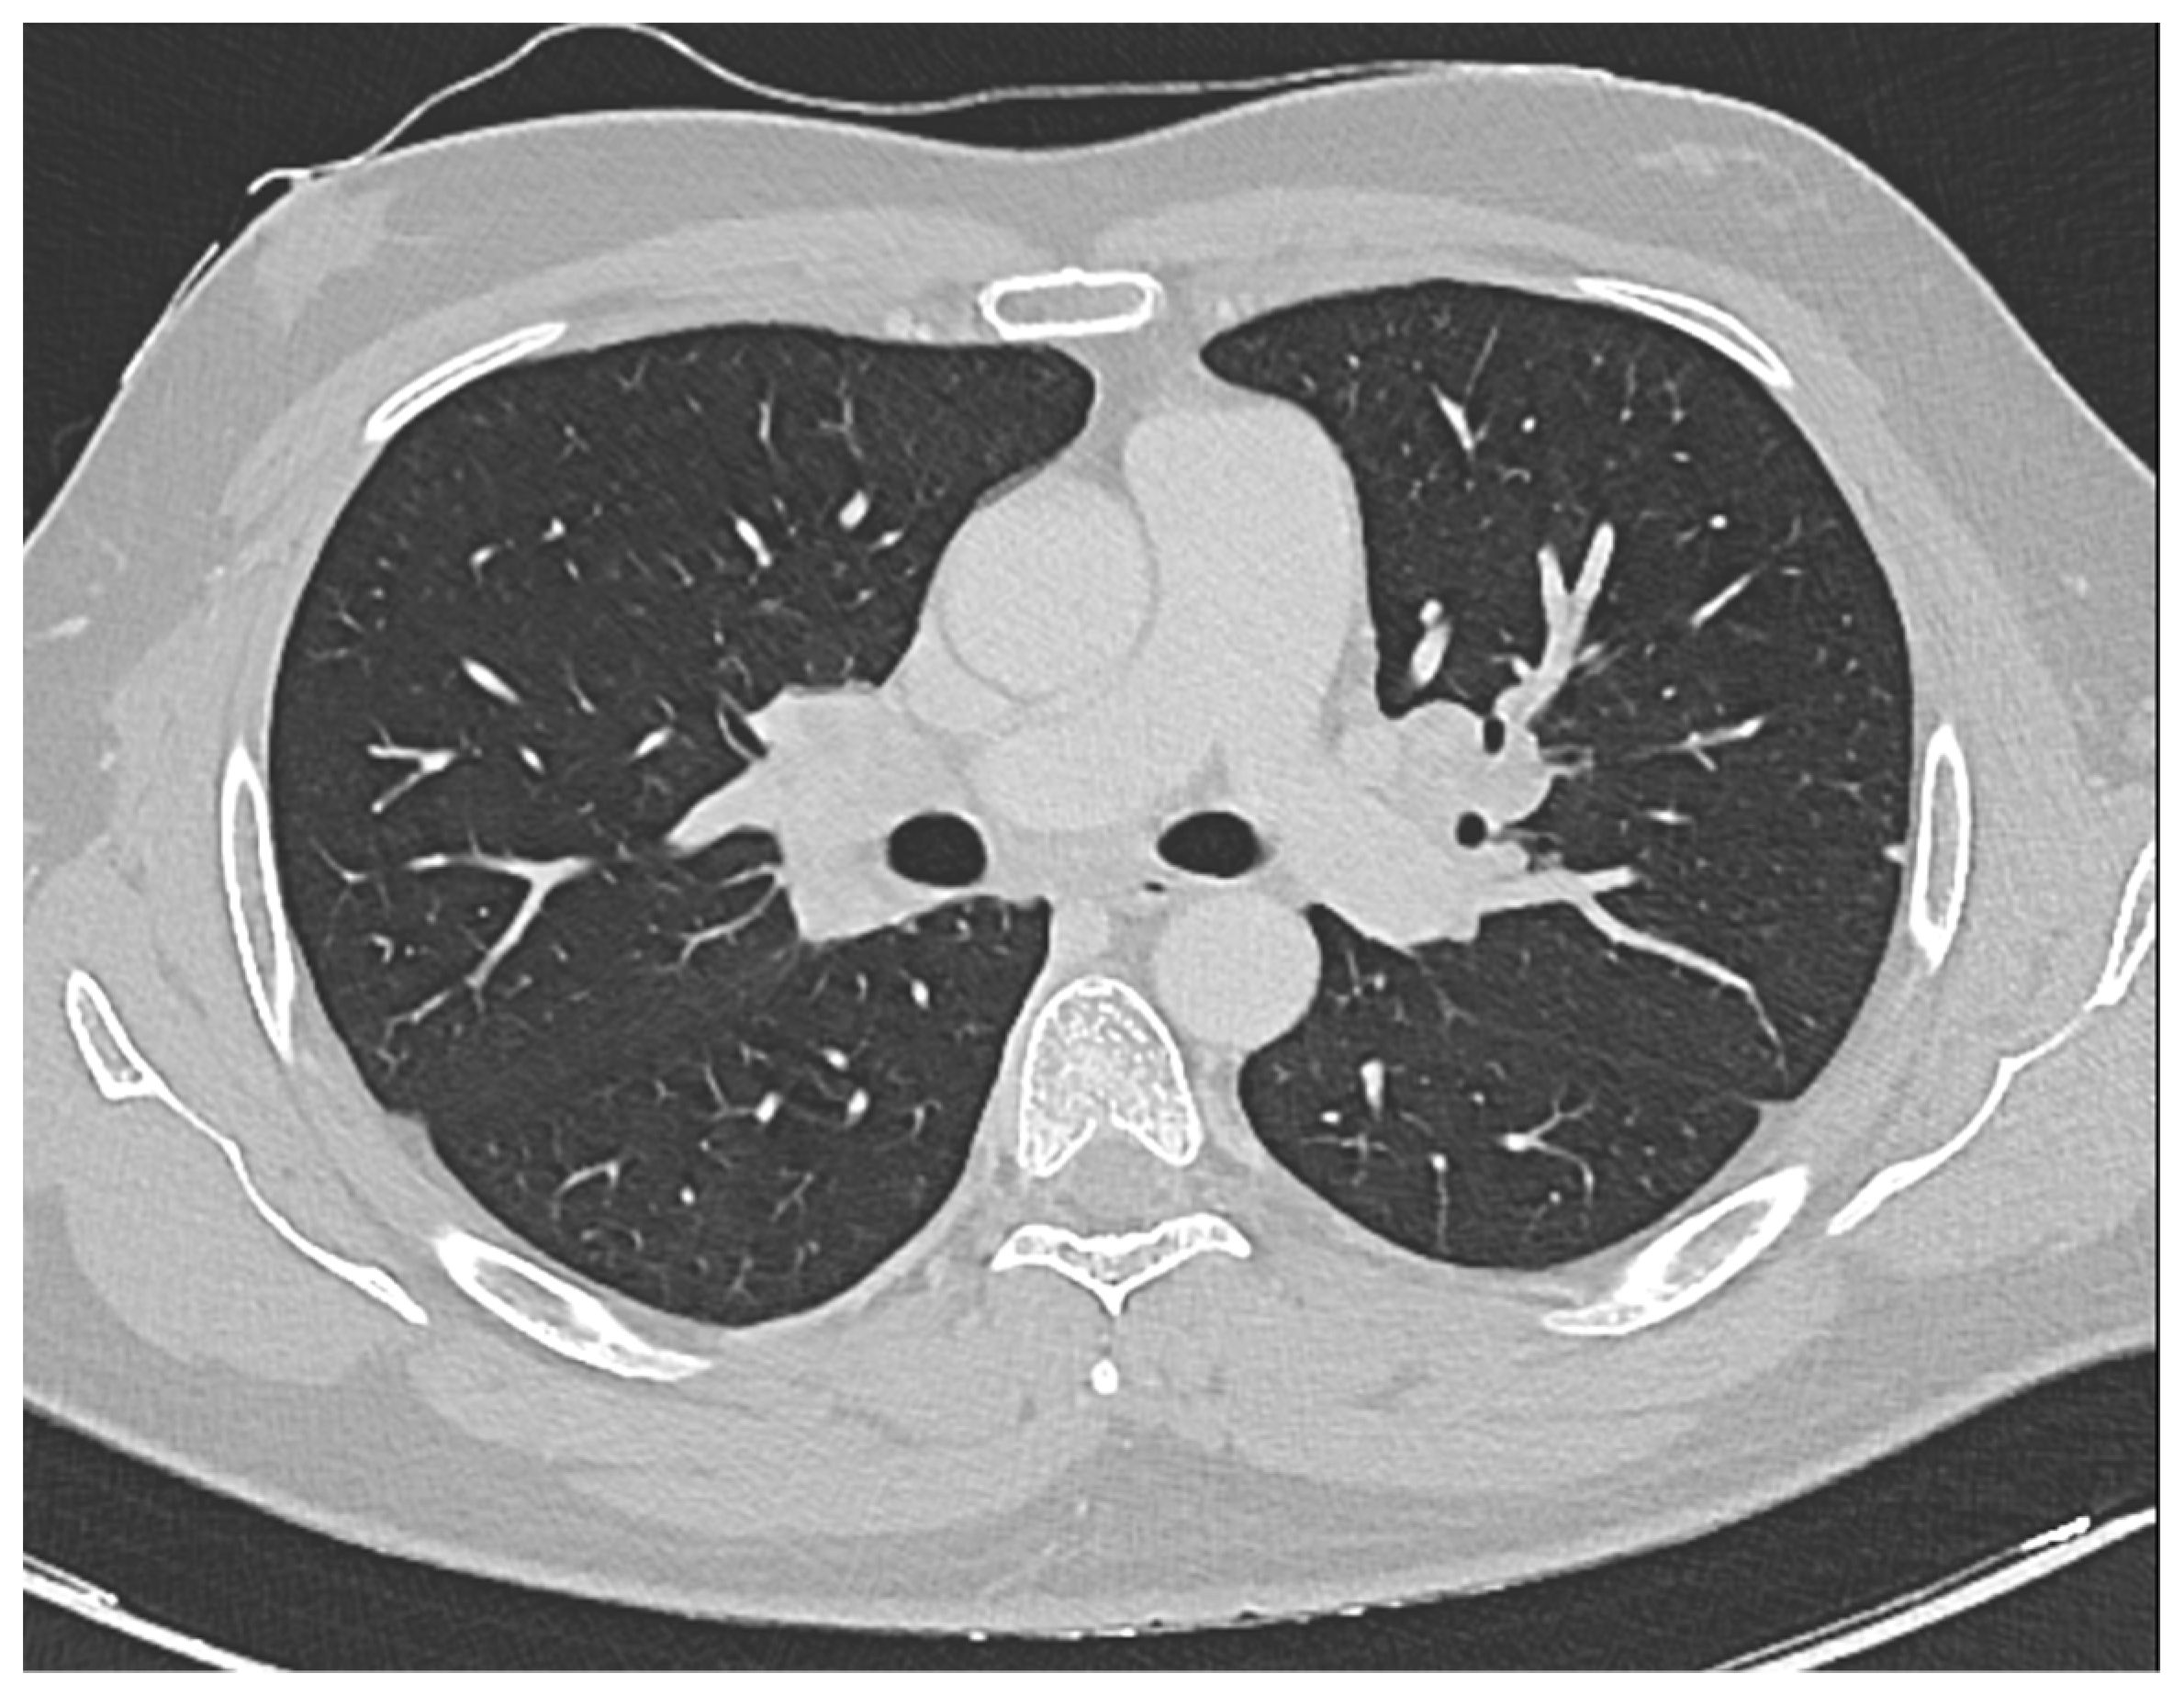

Furthermore, a comprehensive total body CT scan was conducted, which ruled out the presence of adenopathy and adenomegaly. However, within the thoracic region, the scan identified several millimetric parenchymal nodules. These nodules, due to their small size, proved challenging to characterize fully. The largest among them had a maximum diameter of 0.81 cm and was located in the middle lobe. Additionally, there was non-homogeneously hypodense tissue observed in the bilateral hilar area, extending medially to the subcarinal area. This finding raised suspicion of a lymphatic origin and prompted consideration of sarcoidosis as a potential diagnosis (see Figure 1).

Figure 1. CT scan showing the presence of non-homogeneously hypodense tissue in the bilateral hilar area that extends medially up to the subcarinal area, likely of lymphatic origin worthy of cyto-histological evaluation corresponding to Sarcoidosis.